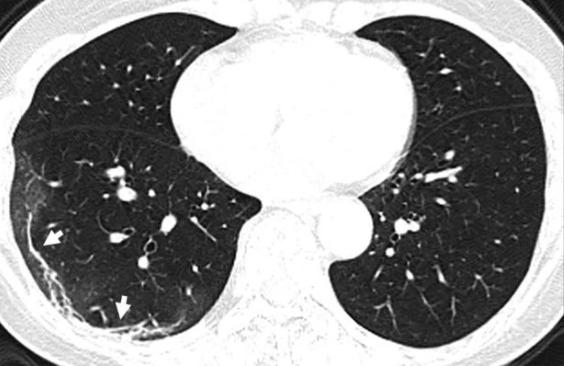

Ảnh chụp phổi của bệnh nhân nữ 54 tuổi.

Ảnh chụp cắt lớp lá phổi của một nữ bệnh nhân 54 tuổi bị nhiễm COVID-19 sau khi đến Vũ Hán cũng cho thấy hiện tượng tổn thương lan rộng như trên. Người phụ nữ này được chẩn đoán viêm phổi nặng do virus corona sau khi có dấu hiệu sốt, ho, mệt mỏi và tức nghẹn ở ngực trong khoảng một tuần. Bác sĩ đã cho bà thở oxy và dùng kháng sinh để đẩy lùi triệu chứng.